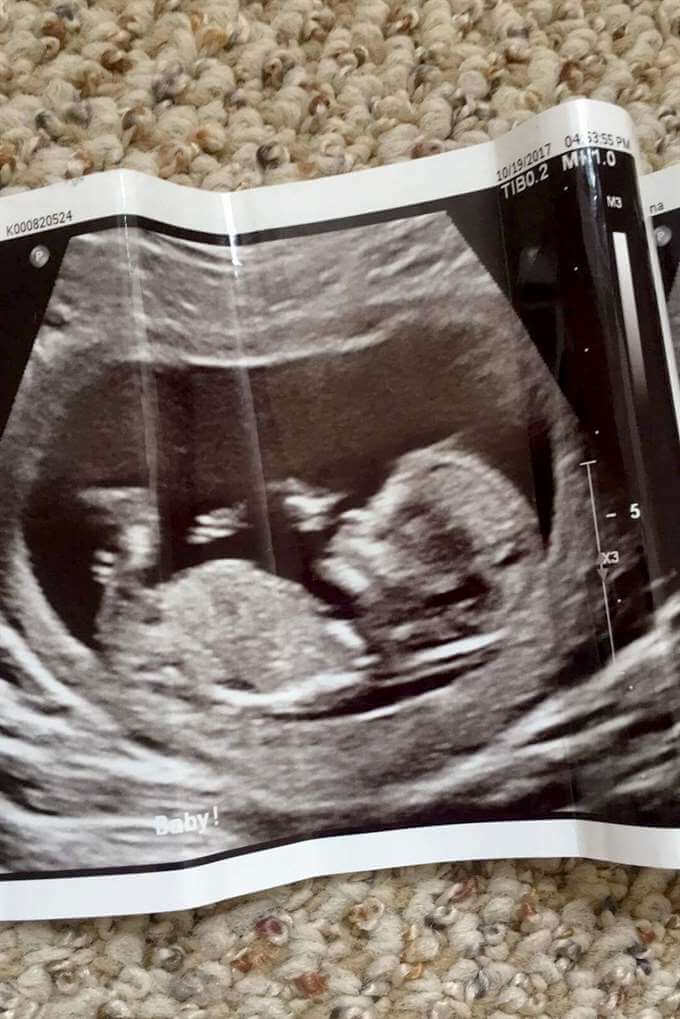

Reanna Stephens är 18 år och gravid. Nu tror många människor att hon har fejkat sin graviditet eftersom vissa tycker hon ser för smal ut för att vara gravid.

Tjejen är 18 år gammal och kommer från delstaten South Carolina som ligger i USA. De brittiska tidningarna har rapporterat om Reanna som är gravid. Reanna menar på att hon är gravid i sjätte månaden, men hon blir mobbad av andra eftersom de anser att hon är för smal för att vara gravid.

Vid ett flertal gånger har 18-åringen fått frågor från främlingar om hon verkligen är gravid eller om hon bara fejkar graviditeten. Hon får även frågor om bebisen mår bra och vissa säger att hon är anorektisk.